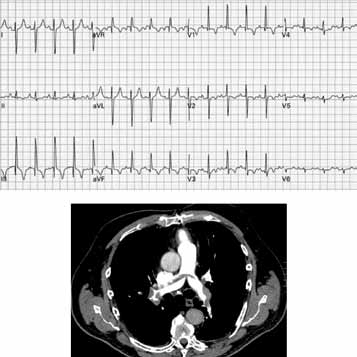

Paciente do sexo masculino, 67 anos de idade, com antecedentes de hipertensão arterial sistêmica, dislipidemia e neoplasia de próstata, submetido a tratamento cirúrgico com prostatectomia radical há 4 anos. Há cerca de 2 dias, relatou início de dor torácica ventilatório-dependente, tosse seca e dispneia limitante em repouso, associada a sudorese e mal-estar. Refere intensificação dos sintomas nas últimas horas, motivando sua procura pelo atendimento médico. O exame físico da admissão mostra o paciente em regular estado geral, taquidispneico em ar ambiente, queixando-se de dor em região retroesternal e base de ambos os pulmões, sudoreico e com extremidades frias, com SO2 = 84%, FR = 36 ipm, PA 80x40 mmHg, FC = 108 bpm. Ausculta cardíaca evidencia apenas ritmo regular taquicárdico. Ausculta pulmonar sem ruídos adventícios. Os exames laboratoriais evidenciaram: Hb = 10,9 g/dL, Ht = 29%, leucócitos = 8 200, plaquetas = 190 mil, ureia = 32 mg/dL, creatinina = 1,01 mg/dL, troponina I = 2,80 ng/dL (VN < 0,16), CKMB = 4,8 mg/dL (VN < 5,0), INR = 1,0, relação de tempos do TTPA = 1,10.

Foram solicitados eletrocardiograma de repouso e tomografia computadorizada de tórax, que se encontram ilustrados a seguir.

A conduta terapêutica inicial mais apropriada ao caso em questão, além de medidas de suporte como expansão volêmica, oxigenioterapia e monitorização, tendo em vista a apresentação clínica e os achados laboratoriais, eletrocardiográfico e tomográfico, será: